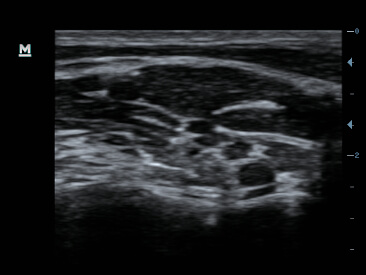

Clinical Images

-CCA & Jugular vien

-Brachial plexus